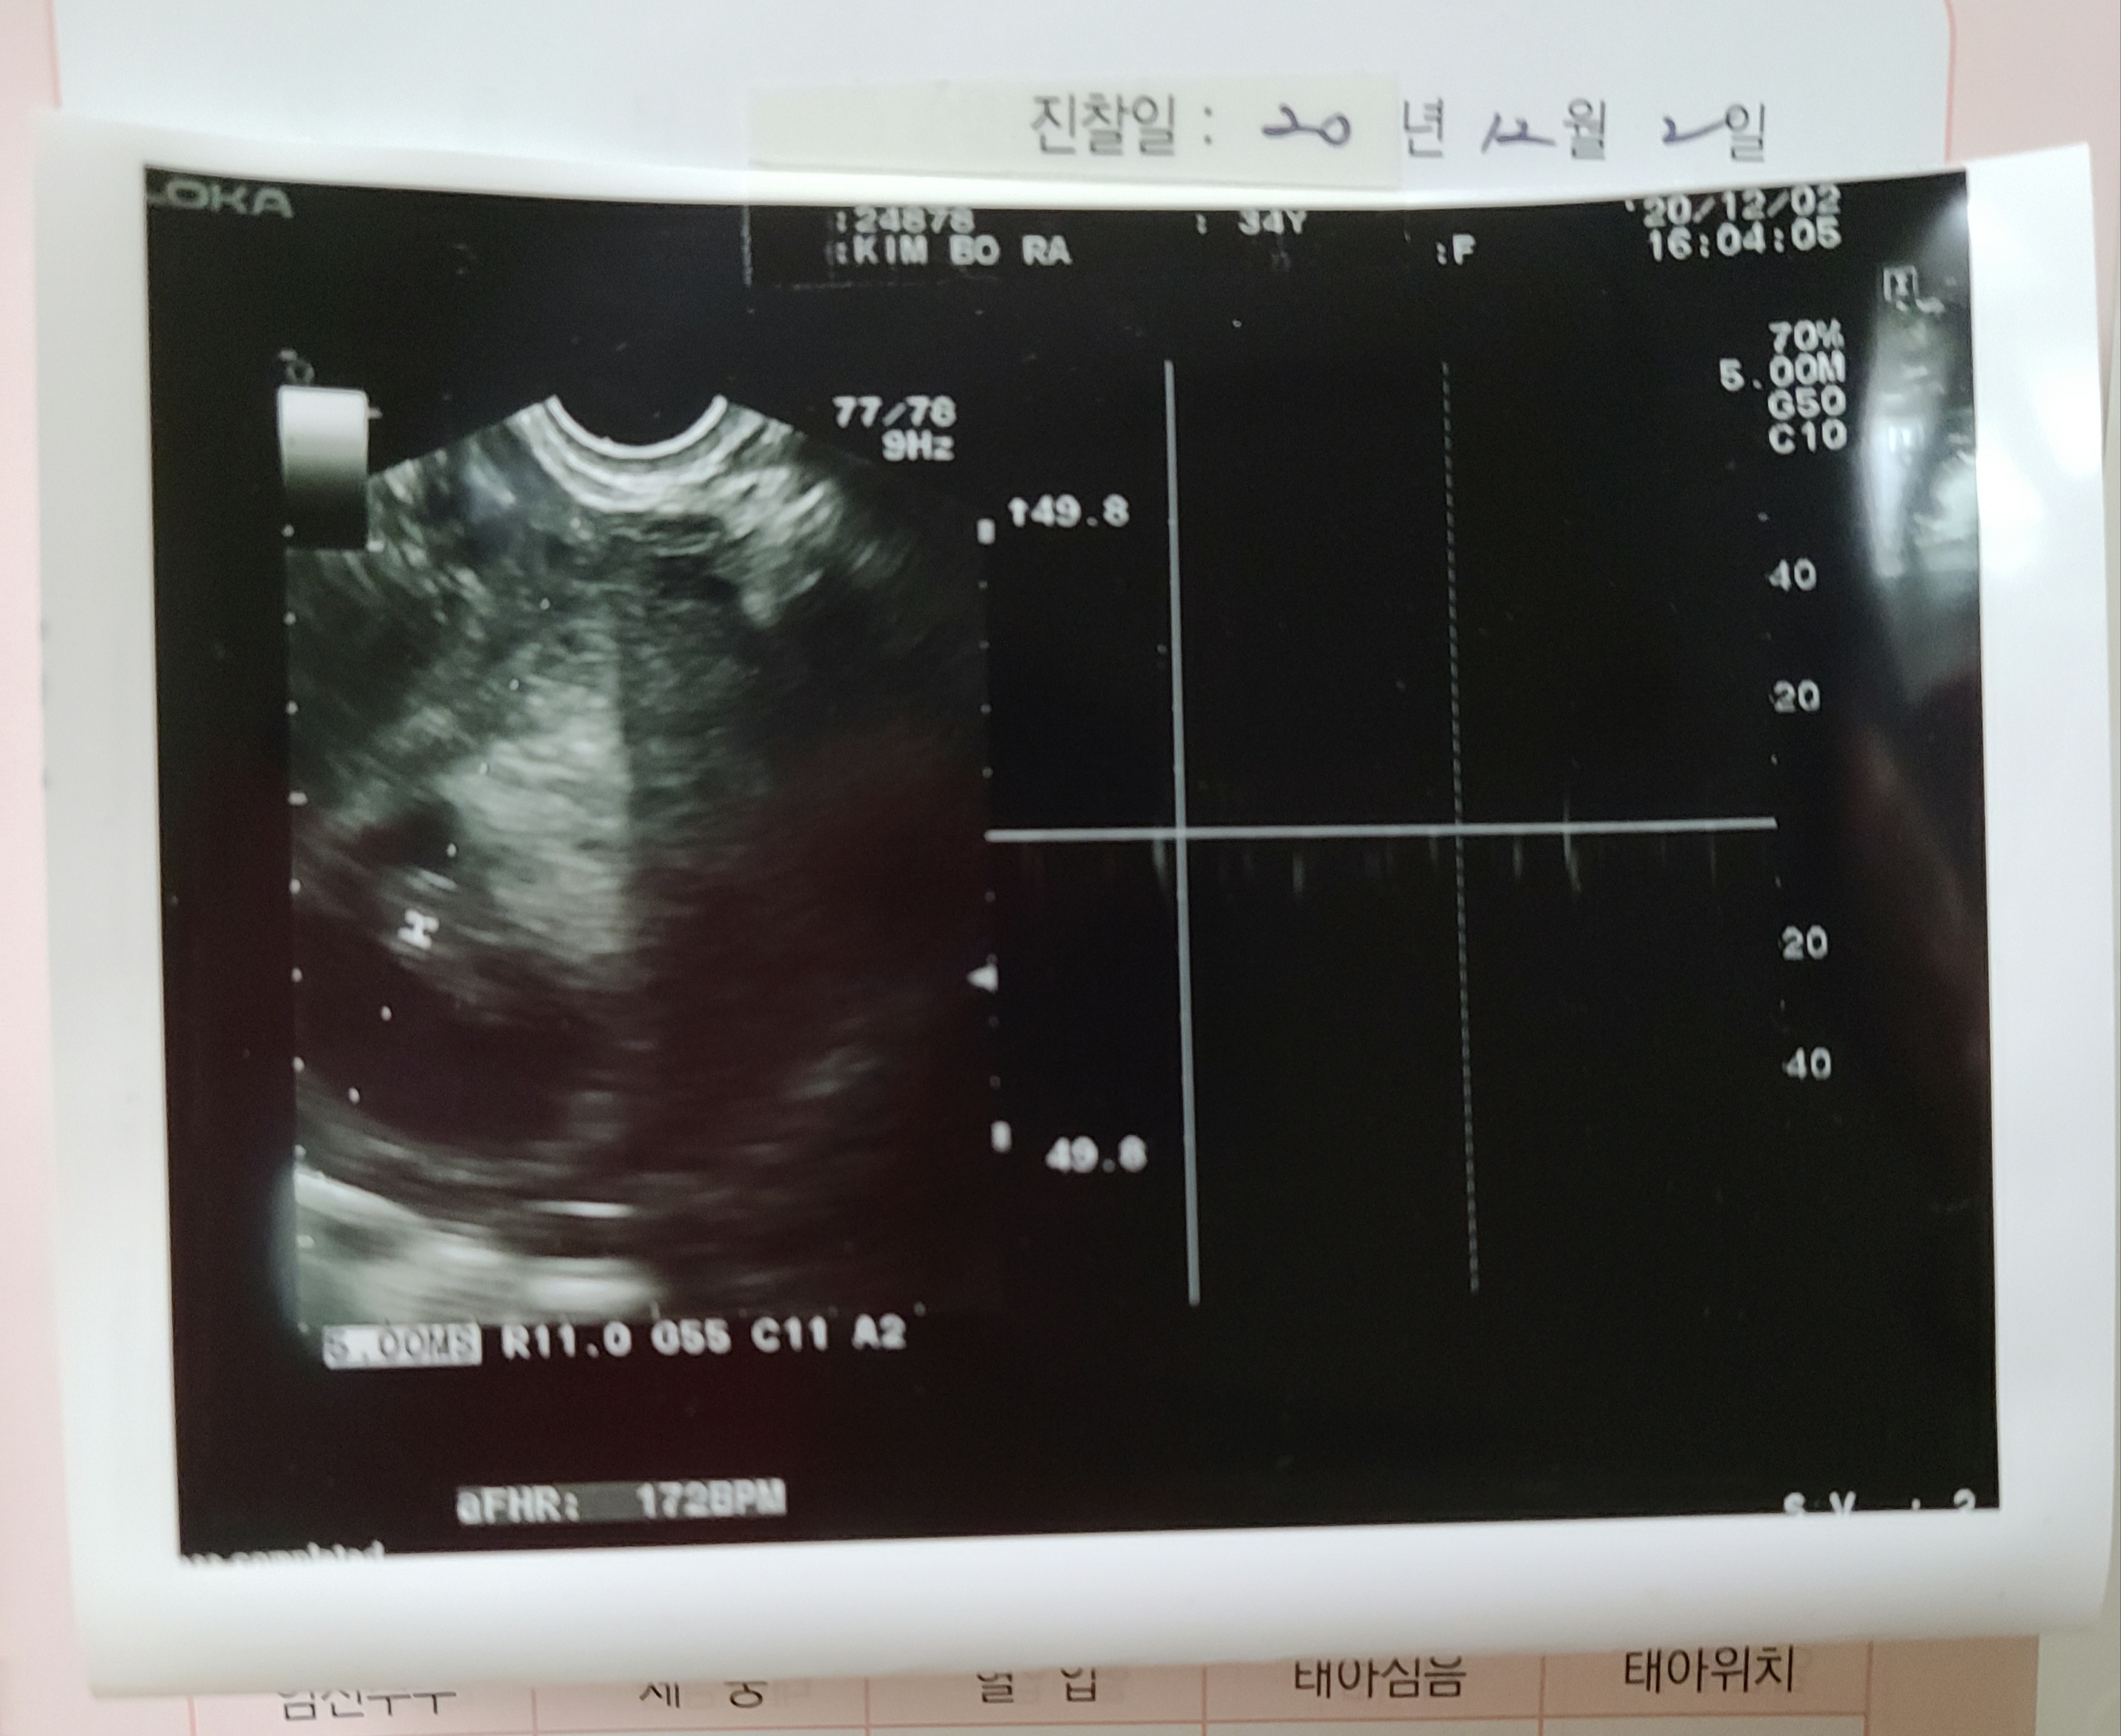

무탈아 오늘 엄마와 아빠는 너무 놀랬단다.

그래서 병원으로 달려갔어

다행히, 건강하게 잘 자라고 있다고해서 안심했단다.

그리고 2.1cm 만큼 커진 무탈이도 보았고.